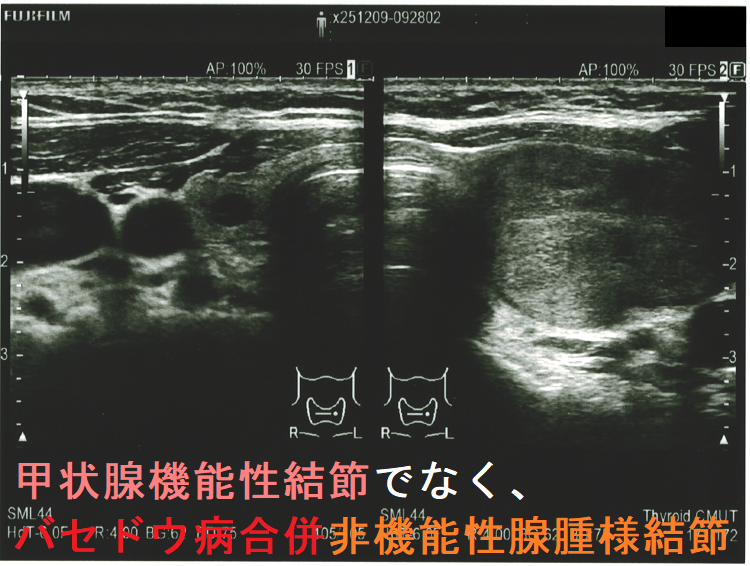

- 甲状腺機能性結節(機能性甲状腺腫)でなく、バセドウ病合併非機能性腺腫様結節だった

超音波(エコー)検査

機能性結節の74.1% は結節内および周辺の血流が豊富ですが、25.9%は周辺の血流のみが豊富です[Radiol Med. 1998 Mar;95(3):193-8.]。